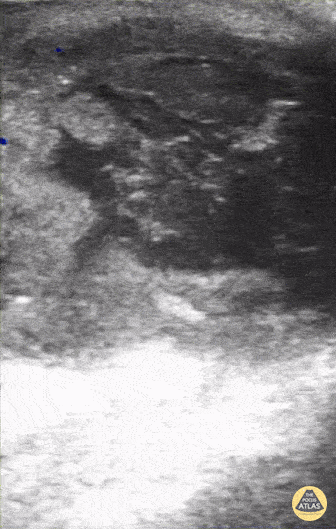

12 year old F with pilonidal abscess. Contributor: Kathryn Pade, MD